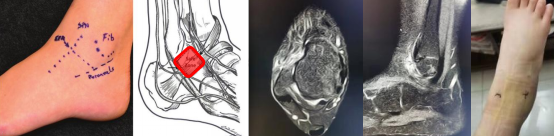

张磊基于“精准医疗与临床转化”相结合的理念,致力于足踝关节创伤、运动及矫形的微创治疗。相继建立系统的踝关节扭伤以及慢性踝关节外侧不稳等技术流程。

开展关节镜下应用ATiFL的远端束转位加强修复治疗踝关节外侧不稳的修复手术和早期康复诊疗方案。

张磊说:“这个技术定位病灶准确,切实解决了临床难点。之前1个小时才能完成的手术,现在打两个5mm的小孔,15-20分钟就完成了。”为超重、运动要求高的患者或质量欠佳的ATFL损伤提供一种新的治疗技术。

14岁学习舞蹈的小女孩右踝扭伤,术后便可自由行走;两年内多次扭伤踝关节的田径运动员,韧带重建后3个月就重返赛场。

2021年,该项目获批四川省科技厅面上项目立项。目前,科室完成踝关节镜及足踝微创手术1000余台。